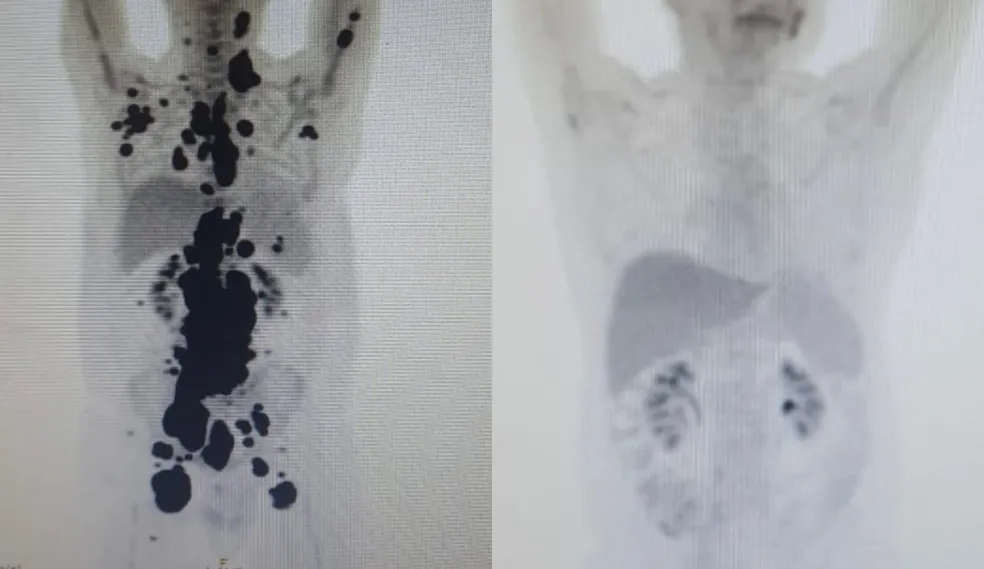

Um dos pacientes beneficiados por esse tratamento é Paulo Peregrino, de 61 anos, que lutava contra o câncer há 13 anos e estava prestes a iniciar cuidados paliativos. Em abril, ele passou pelo tratamento e, em apenas um mês, obteve uma remissão completa do seu linfoma.